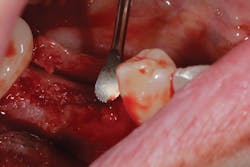

Although unpredictable, a greater amount of alveolar ridge loss following extraction usually occurs in the horizontal dimension and affects the buccal bone of the ridge.3 In fact, 50% of alveolar bone dimension can be lost after tooth extraction, with losses reported of up to 6–7 mm (figure 1). Two-thirds of this loss of bone volume can occur within the first three months of tooth extraction.4

Because of this alveolar resorptive pattern after tooth extraction, bone grafting the extraction socket after tooth extraction procedures has become a solution that attempts to limit the amount of hard- and soft-tissue loss. There are many systematic reviews in the literature that compare the results of residual ridge dimension following tooth extraction after the use of a bone graft (with or without a membrane) versus extraction alone without grafting.7